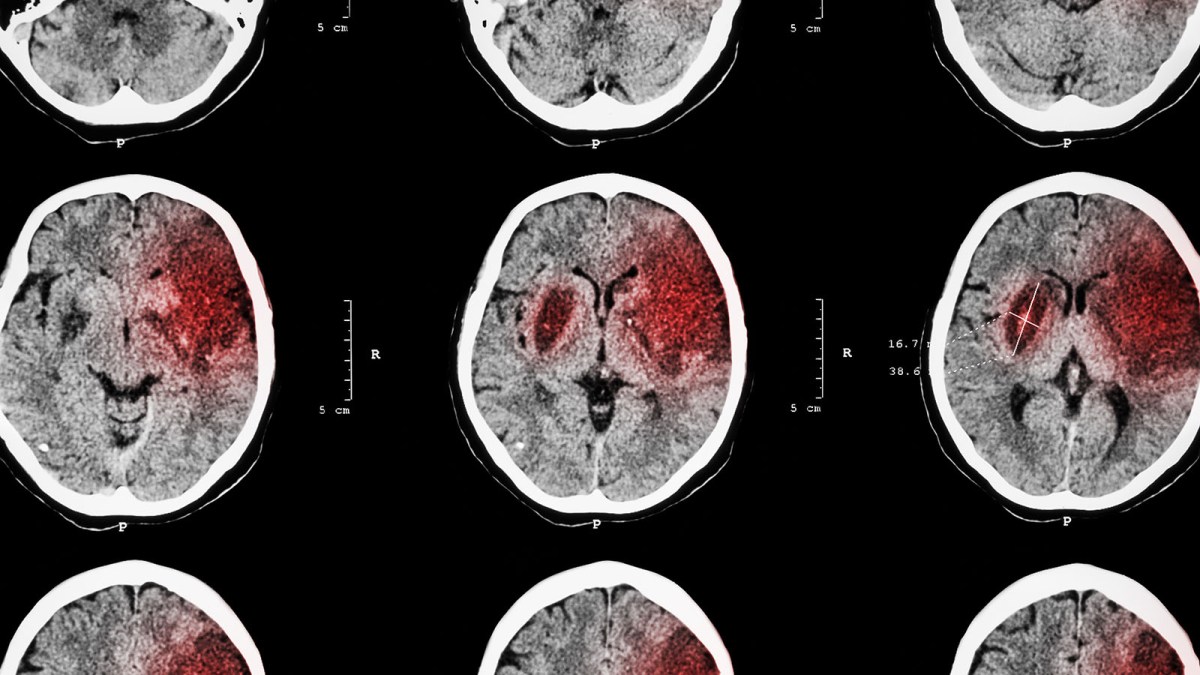

Stroke recovery: An ischemic stroke is caused by a clot choking off blood supply to part of the brain, leading to the death of brain cells in the impacted region.

This can lead to long term complications, including loss of muscle use, difficulty talking and swallowing, and emotional and memory issues.